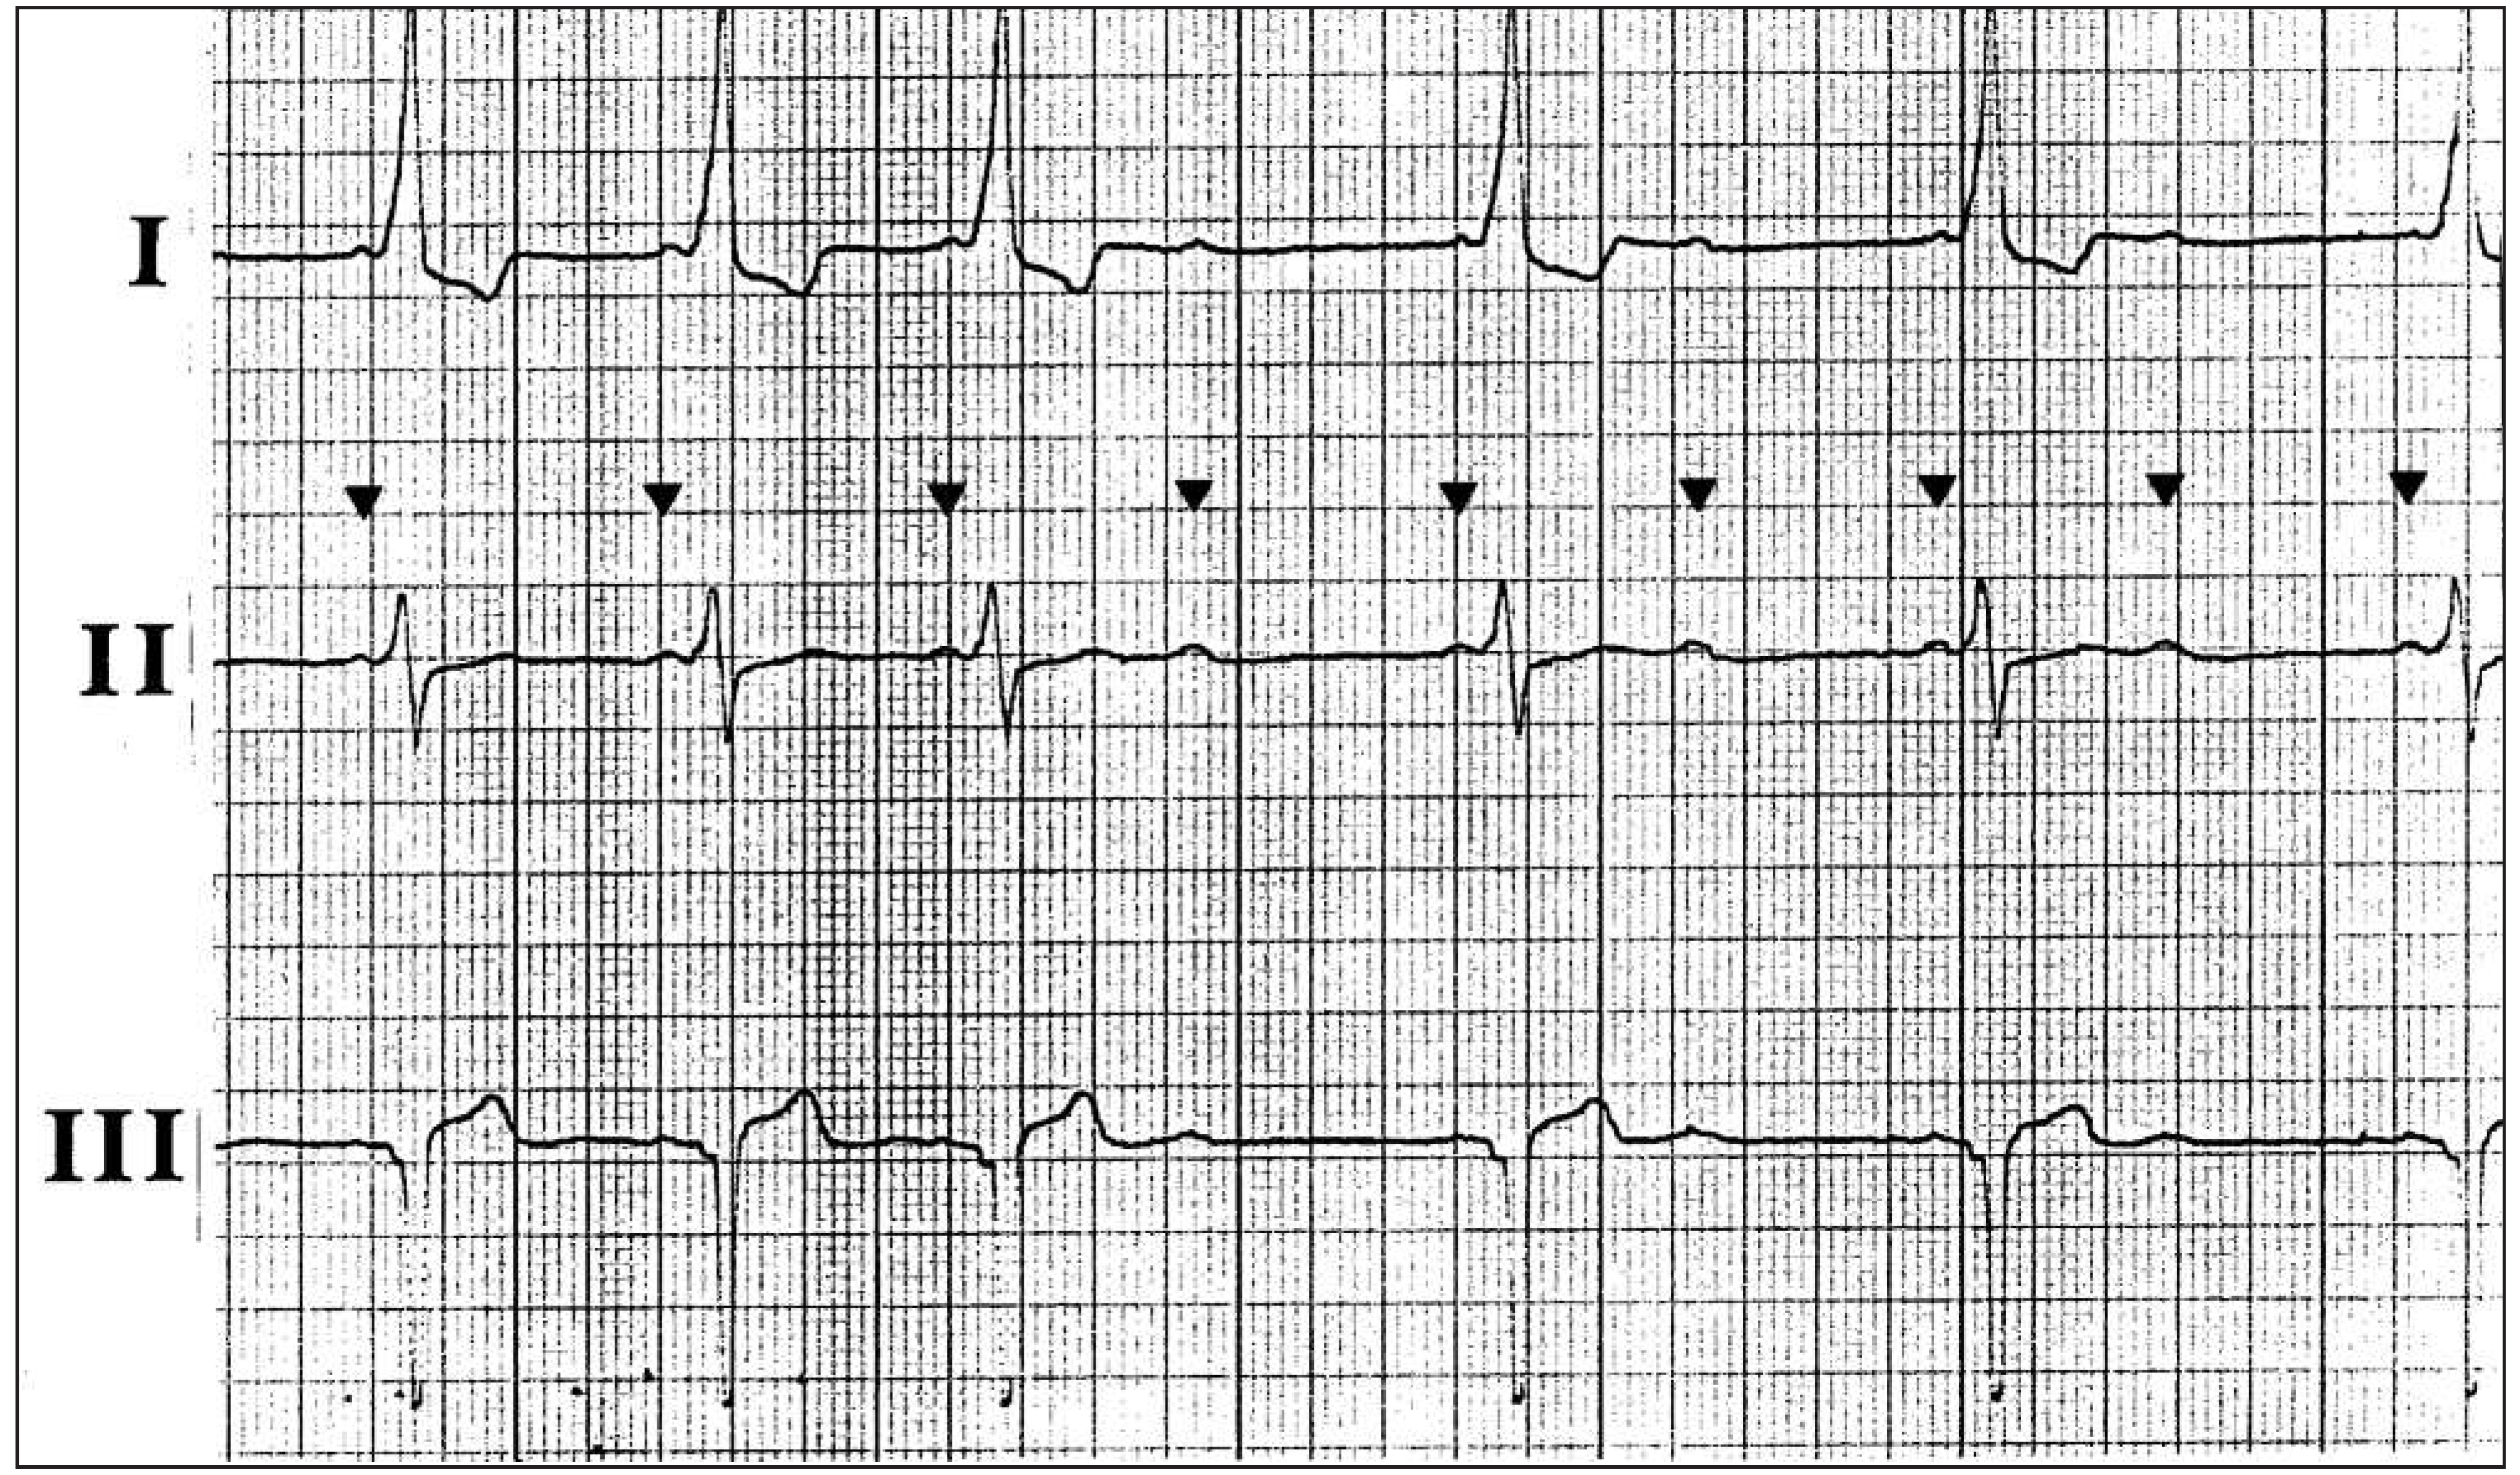

Dyspnoea in a Patient with Alternating Rhythms

1. Case Presentation

2. Questions

- What is your diagnosis?

- What treatment should be proposed?

3. Commentary